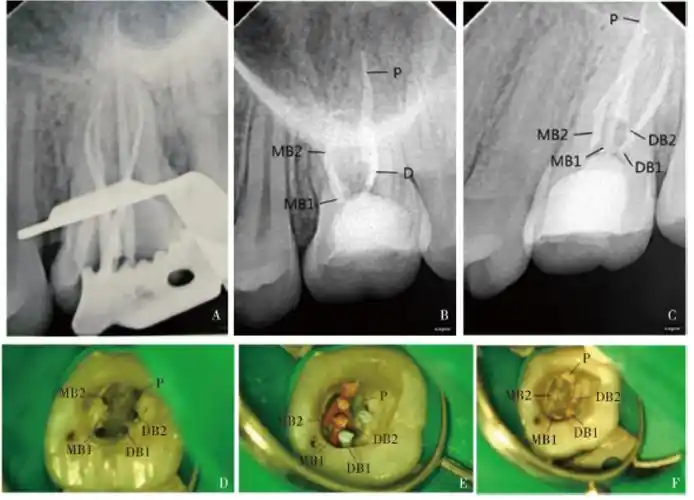

上颌第一磨牙远颊双根管1例

罕见上颌第一恒磨牙6根管的病例报告暨plex锉的根管治疗之路济南博士

上颌第一前磨牙4根管1例